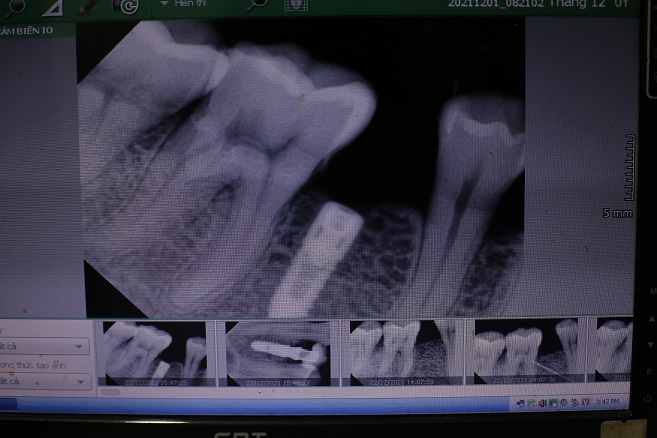

– Trường hợp 1: Khi có răng hư cần phải nhổ sớm

Trong trường hợp nếu bạn có các răng bị hư cần phải nhổ, thì tốt nhất nên nhổ càng sớm càng tốt vì bệnh lý của răng sẽ làm tiêu xương hàm rất nhanh và nên nhổ với kỹ thuật đặc biệt để tránh làm tổn thương xương ổ răng.

– Trường hợp 2: Ngay lúc nhổ răng

Nên đặt Implant ngay lúc nhổ răng nếu tình trạng xương, nướu cho phép (đặc biệt là vùng răng cửa) nếu không thì đặt Implant sau một vài tháng khi vết nhổ đã lành thương.

– Trường hợp 3: Khi răng bị nha chu không giữ được và cần nhổ

Khi răng bị nha chu không thể giữ được, hoặc không thể vệ sinh tốt được thì phải nhanh chóng nhổ đi để tránh nhiễm trùng và tiêu xương lan rộng, khi nhổ có thể trồng răng Implant ngay, hoặc nếu thiếu hổng xương quá nhiều thì cần ghép xương lúc nhổ để tiến hành đặt Implant sau đó vài tháng.